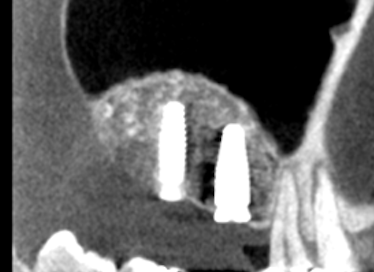

| 主訴 | 左で上手くものが噛めない 右上奥から膿が出ている |

右側の咬合過多により上顎臼歯の歯根破折を認めた